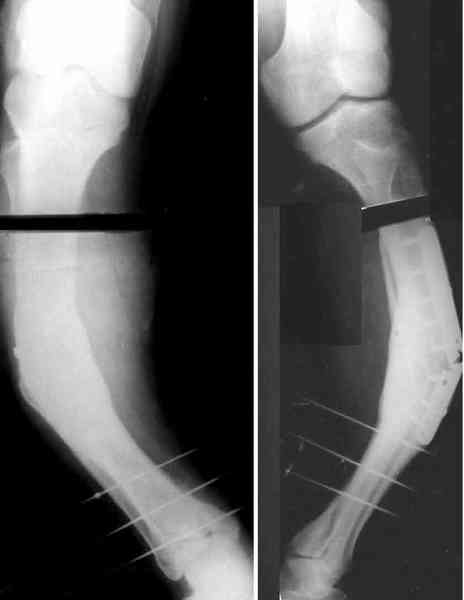

Для продолжения темы - несколько картинок.

Пациент 30 лет, лет пять назад оперирован по поводу перелома голени пластиной. Находясь на героине, нарушил режим, пошел, сломал и ногу и

пластину, но перелом сросся.

В приложении - внешний вид и рентген.

Мнения?

Лукавить не буду, я его уже вылечил. Но применил немного необычную тактику по отношению к пластине - результат после обсуждения...

Пластинку и винты мне удалось разглядеть только на профильной проекции, точнее, трехчетвертной, судя по виду коленного сустава (правый снимок). На фасной - вообще не могу разобрать, где она :( Но, в конце концов, можно и не видя ее сказать, что уровень остеотомии может быть и другим, ниже или выше пластинки, придется только компенсировать смещение по ширине, которое появится при полном устранении угла не на вершине.